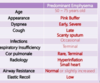

Define toxic shock and explain the mechanism behind it.

- What does extracellular bacterial infection produce that causes a toxic shock?

- What do T-Cells bind to because of the superantigen? What does this lead to? Is this specific binding, or non-specific binding?

- What do patients usually present with?

- What organism is the usual cause?

Define toxic shock and explain the mechanism behind it.

- What does extracellular bacterial infection produce that causes a toxic shock?

- Results from the production of a superantigen.

- What do T-Cells bind to because of the superantigen? What does this lead to? Is this specific binding, or non-specific binding?

- Superantigen causes binding between host T-cells and MHC II receptors. Helper T cells express CD4 molecules, which bind to MHCII on antigen-presenting cells.

- This interaction leads to the release of cytokines and further immune system activation.

- This nonspecific binding between host T cells and MHC II receptors by the superantigen leads to massive T cell activation.

- What do patients usually present with?

- Massive T cell activation with the release of cytokines leads to fever, hypotension, and a defuse sunburn-like rash.

- Classically the nidus for infection is from a forgotten tampon in the vagina, but the most common presentation to clinics is from nasal packing after a nosebleed that has been kept in for too long.

- What organism is the usual cause?

- Staphylococcus aureus is the most common cause, although β-hemolytic group A streptococci can cause a similar presentation.